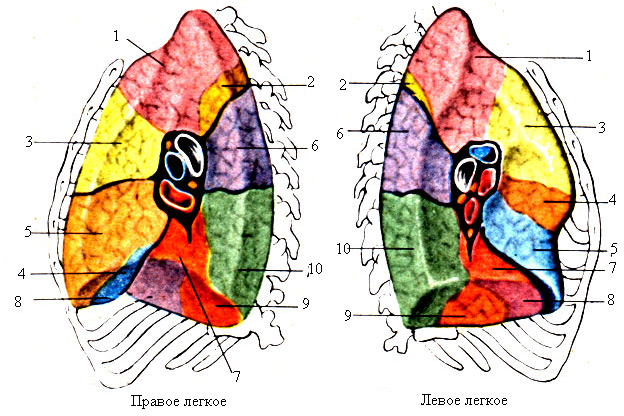

Анатомические изображения сегментов легких различных животных

Раздел: Другие животные